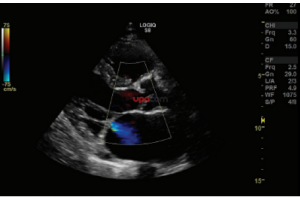

- Система Logiq S8 GE Healtcare, производства Россия – это уникальная ультразвуковая система экспертного класса, компактная и мобильная, удобная в эксплуатации.

- B-режим, M-режим, PW допплер, цветовое допплеровское картирование и энергетический допплер, кодированное излучение, кодированную тканевую гармонику.

- Программы измерений и отчетов для всех областей применения;